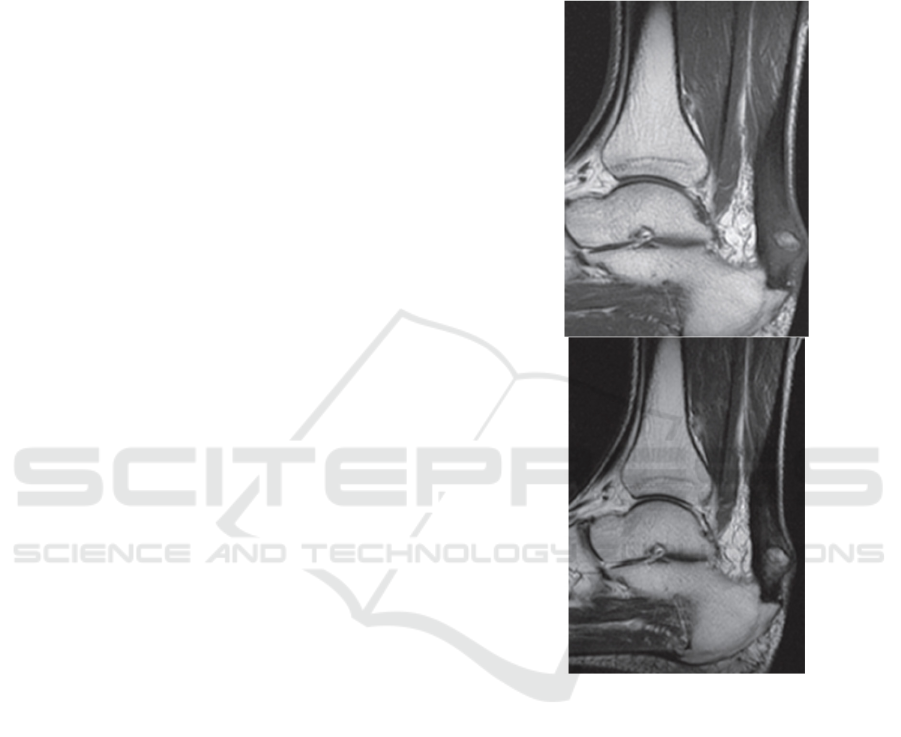

The MRI manifestations of complete Achilles

tendon tear include retraction of the rupture end, and

the width of the rupture crack reflects the degree of

retraction of both ends. The ruptured fibrous bundles

interlock and overlap with each other in a "brush"

shape, and the ruptured fibrous bundles retract in a

"oak" shape. When the torn tendon retracts

significantly, it can appear wavy. MRI manifestations

of incomplete Achilles tendon tear: Partial Achilles

tendon tear, with a stripe like, patchy, and focal high

signal shadow at the tear site compared to normal

Achilles tendon. Incomplete Achilles tendon tear

shows continuity on at least one level. Partial

incomplete tearing occurs on the basis of certain

lesions, as shown in Figures 1 (Xiao et al., 2014).

Figure 1: MRI manifestations of incomplete Achilles

tendon tear.